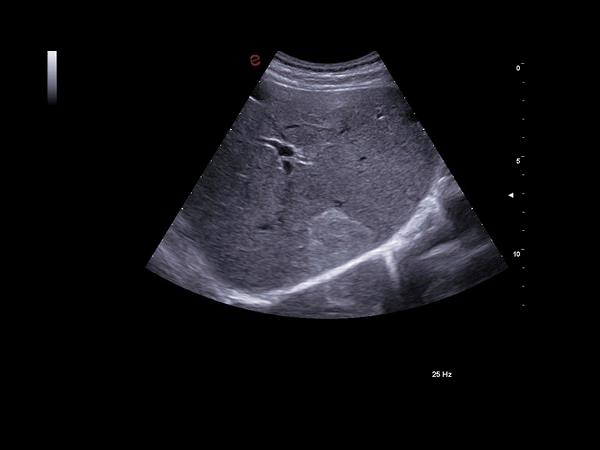

Med sine avancerede funktioner og høje billedkvalitet er MyLab™A70 ideel til et bredt spektrum af anvendelsesområder, fra akutte traumer til komplekse vurderinger. Den intuitive brugerflade gør betjeningen enkel, og de AI-drevne værktøjer hjælper med scanningsarbejdet og lader dig fokusere på patienten.

De indbyggede AI-værktøjer hjælper med automatisk billedoptimering og arbejdsflow, fx eScan, Autoscan og eDoppler. Derudover understøtter A70 avancerede målinger som strain-analyse og lever-elastografi.